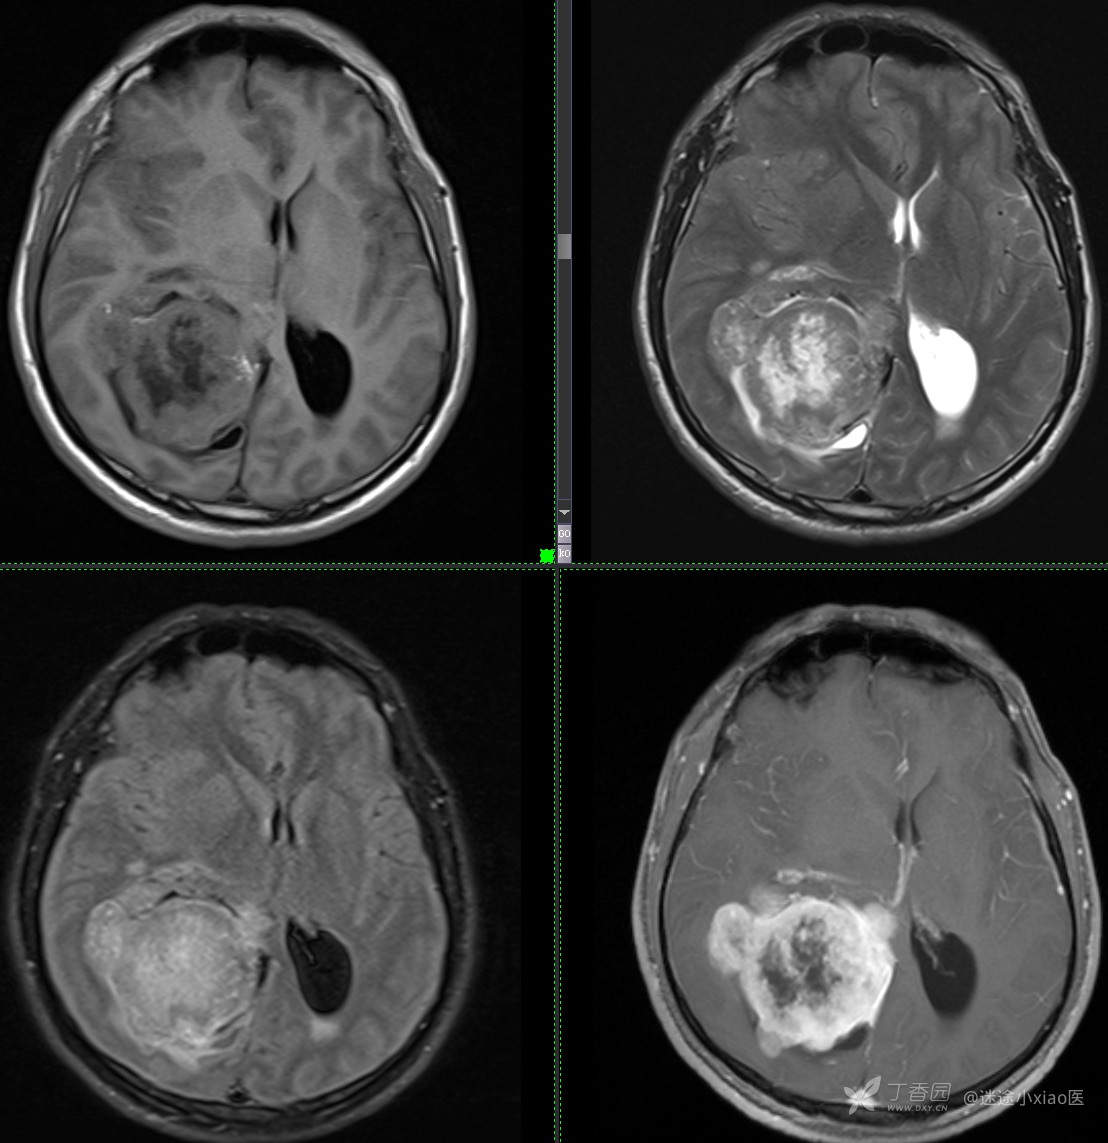

患者年龄:43

患者性别:男

简要病史:头痛3月余,查体无殊